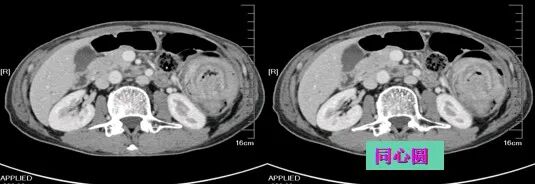

肠套叠

肠套叠是指一段肠管套入与其相连的肠腔内,并导致肠内容物通过障碍。肠套叠占肠梗阻的15%~20%。有原发性和继发性两类。原发性肠套叠多发生于婴幼儿,继发性肠套叠则多见于成人。绝大数肠套叠是近端肠管向远端肠管内套入,逆性套叠较罕见,不及总例数的10%。

降结肠癌并肠套叠